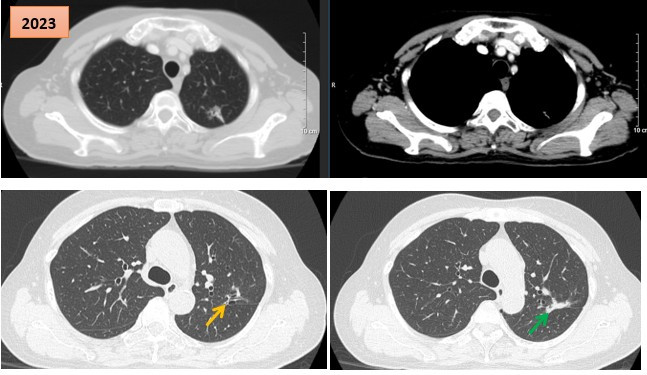

Bệnh nhân ghép phổi đầu tiên ở phía Nam xuất viện trong tình trạng khỏe mạnh

Wednesday 2025-12-10 03:52Bệnh viện Chợ Rẫy vừa ghi dấu cột mốc đặc biệt trong lịch sử ghép tạng khi nam bệnh nhân A. (sinh năm 1986, ngụ TPHCM) - người được ghép phổi thành công trong đêm 7/11 rạng sáng 8/11 đã chính...